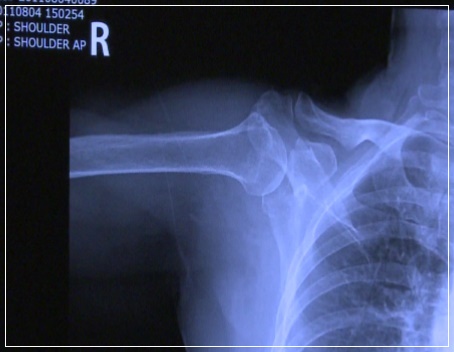

오십견은 비교적 흔한 병이라 쉽게 생각할 수 있지만 방치하다 치료시기를 놓치면 후유증이 커질 수 있습니다. 또한 회전근개 파열, 석회화 건염, 목 디스크 등 다른 원인이 될 수 있는 질환과 구별을 해야 하기 때문에 통증 초기에 정확한 진단적 검사와 진료를 받는 것이 필요합니다. 치료하지 않을 경우 증상이 1~2년 이상 지속되어 생활에 많은 불편을 초래할 수 있습니다.